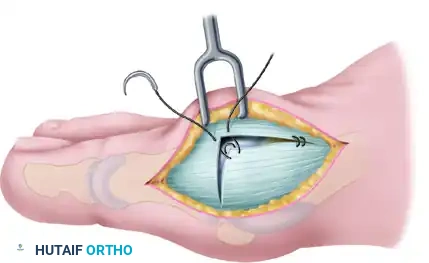

Step 3: The Inverted-L Capsulotomy

To maximize the effectiveness of the revision capsular imbrication, an extensive dorsal exposure is required. Commonly, a thin slip of accessory extensor tendon is visible; this serves as a helpful anatomical landmark. If absent, locate the dorsal and medial juncture of the rounded distal first metatarsal head.

Using either the medial aspect of the accessory tendon or the dorsomedial border of the first metatarsal as a starting point, perform an inverted-L capsulotomy. Complete a capsular-periosteal excision from the first MTP joint line extending proximally to the junction of the middle and distal thirds of the metatarsal.

Begin the transverse limb of this incision exactly at the joint line. Applying axial traction on the hallux helps to identify the distal edge of the metatarsal head, preventing inadvertent scoring of the articular cartilage with the scalpel. The transverse limb extends from dorsal to plantar through the capsule and the conjoined capsular-abductor hallucis tendon insertion, terminating 2 to 3 mm medial to the tibial sesamoid.

Step 4: Capsular Flap Elevation

With a small, pointed blade (e.g., a #15 blade), carefully raise the medial capsule from the underlying bone. Begin at